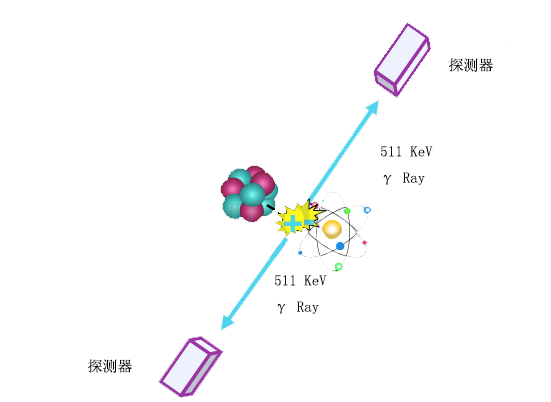

加速器产生的不稳定核素,会自发释放出正电子β+,与病灶附近的β-电子发生“湮没辐射”,发射出两个能量相等、方向完全相反的γ光子,探测器根据采集到光子信号的时间差,准确定位病灶位置。

“湮没辐射”也是爱因斯坦E=mc2阐述的质量和能量之间转换的一种表现。